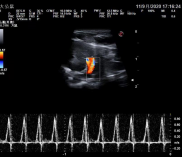

猫动脉